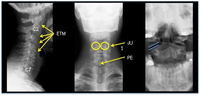

Coluna cervical normal: incidências lateral, anteroposterior (AP), e odontoide com boca aberta